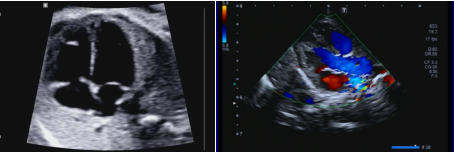

小儿心脏超声检查是一种无创、无痛、无辐射的检查方法,利用高频声波对心脏进行观察和检测。可以反映心脏结构上的有没有异常,测量心房、心室大小,观察室间隔、房间隔连续性及室壁厚度;观察心瓣膜开放关闭的情况,有没有合并狭窄或关闭不全;还可测量计算出左室的射血分数,评价心脏的功能。